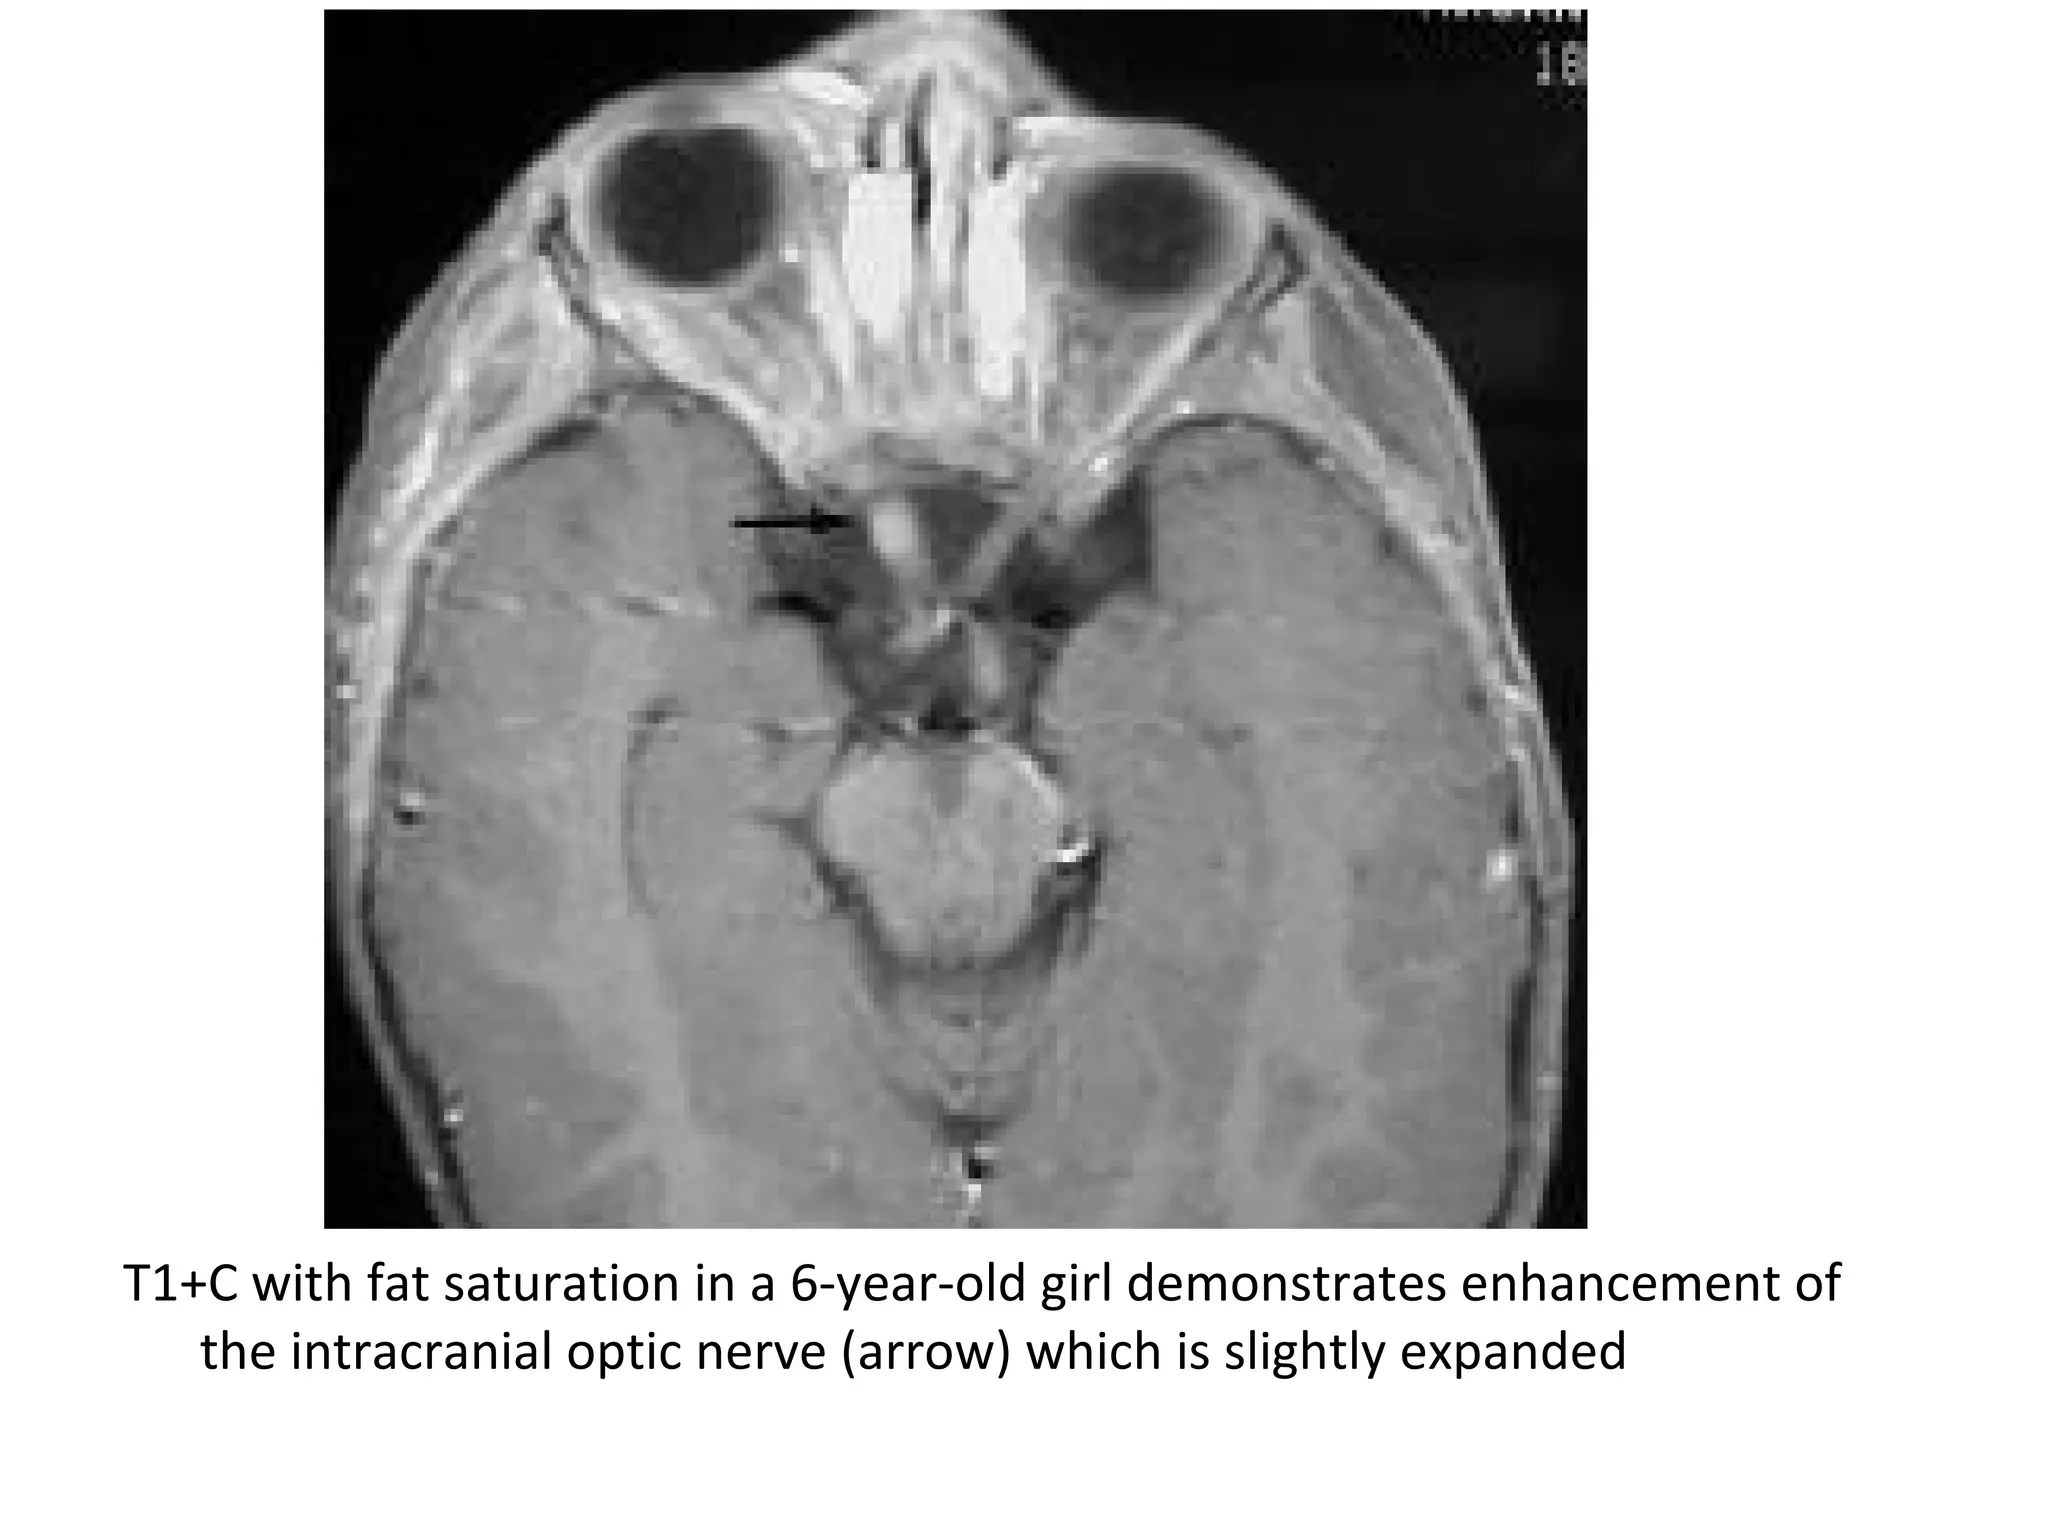

T1+C with fat saturation in a 6-year-old girl demonstrates enhancement of

the intracranial optic nerve (arrow) which is slightly expanded

T1+C with fatsaturation in a 6-year-old girl demonstrates enhancement of the intracranial optic nerve (arrow) which is slightly expanded